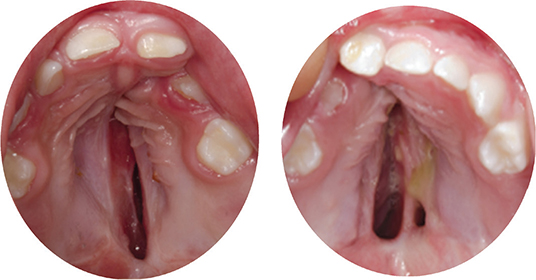

The width of the infant cleft (baseline width) was measured with a digital calliper along the inter-tuberosity line on study casts obtained before SPC (T0). The cast models obtained before HPC (T1) were digitised using a plaster model scanner (OrthoX Scan) with the base of the cast, resting at the model holder and fitted on the magnet retention. The STL files were imported and analysed in the software program Blender 3.6 LTS, to assess area, width and length of the residual cleft. The three-dimensional model of the maxilla was aligned by rotating the model to position the cusp tips of one primary tooth in each lateral segment and one primary central to fit the same horizontal plane (Figure 2a). Viewing the cleft along the axis orthogonal to the horizontal plane, the outline of the cleft was sketched. The contour of the cleft was delimited anteriorly by the outline of the most anterior part of the clinically visible cleft and the inter-tuberosity line posteriorly, and the area was calculated by the software program (Figure 2b). The nonvisible cleft was considered to be functionally closed and was therefore not included in the measurable cleft. The length and the width of the cleft were quantified using a Matlab script (Figure 2c), where the length of the cleft was defined by its extent in the sagittal direction. The width was assessed dividing the cleft into four quartiles (Q1–Q4) perpendicular to the sagittal line, and the maximum width of the cleft in each of these quartiles was calculated. Clinical photographs taken at the same time as the study cast (T1) were examined to identify residual clefts occurring bilaterally of vomer (Figure 3). The assessment was repeated after 3 weeks, for 30 cases to calculate the intra-rater reliability.

Figure 3. Examples of residual clefts prior to hard palate closure, occurring (a) unilateral of vomer and (b) bilateral of vomer posteriorly.

The assessments of the clinical photographs identified eight cases out of 37 solely in GBGmod, with residual clefts occurring posteriorly, bilaterally of vomer.